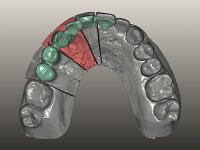

Fixed partial denture between teeth 15 and 11, using teeth 14, 13 and 11 as abutments. Teeth 12 and 15 were planned as ovoid pontics. The framework material chosen was zirconia and the veneering ceramics should have a gum-shade component to rehabilitate the soft-tissues.

After the root canal treatment of tooth 11, dental impressions were taken to do a fixed provisional (reinforced) acrylic prosthesis. The provisional bridge included an acrylic component with a gum-shade color, to evaluate the integration of the treatment plan, in relation to function and esthetics. The preparation of teeth 14 and 13 were minimal invasive, with supra-gingival finishing lines, preserving enamel at its uttermost. Tooth 11 was prepared in a conventional way, with an intra-sulcular margin. The provisional bridge was rebased intra-oral with an autopolymerized acrylic. After 4 weeks, a dental impression with a double mixture technique was done. In the dental lab, CAD-CAM technology was used to produce a zirconia framework. In the provisional bridge, it was noted by the patient, and by ourselves, the need for symmetry in the dimensions and shape of the teeth, in relation to their homologues of the 2nd quadrant. Accordingly, a mirror effect was selected in the CAD design of the framework, to mimic in the prosthetic structure the dimensions and shape of the homologous natural teeth. Framework design included also a small zirconia wing covering the palatal surface of the non-prep tooth 21. This wing serves as an additional support and, simultaneously, avoids an eventual occurrence of a future diastema between central incisors. Color selection of teeth and soft-tissues was done by the ceramist in the dental office. After evaluation and approval of the prosthetic work placed in mouth, the dental bridge was bonded. This bonding procedure was optimized by the addition of a zirconia liner in the inner surface of the framework and in the internal surface of the wing. This treatment proved to be esthetically acceptable and functionally able, with a strong contribution to the patient’s self-esteem.